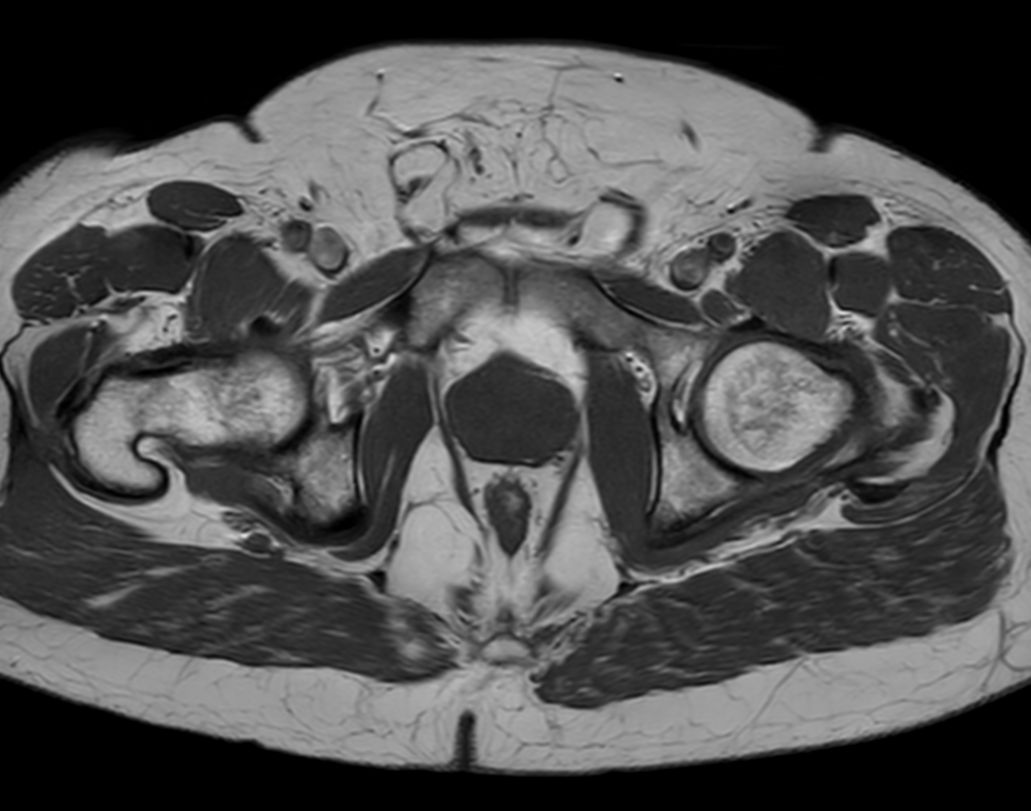

Axial T2w TSE

Axial 3D T2w TSE (PelvisVIEW)

Coronal T2w TSE